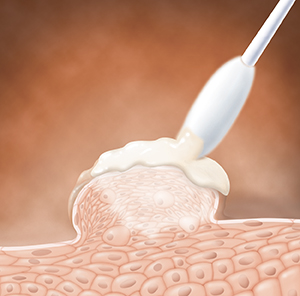

Medicines

Prescription creams and gels can be applied to warts and nearby skin. Some prompt your immune system to fight against HPV (human papillomavirus), the virus that causes genital warts. Others are strong substances that destroy warts. Medicines can be applied at the healthcare provider's office or at home. Often more than 1 dose is needed. These treatments sometimes cause skin rashes. Talk with your healthcare provider about possible side effects.